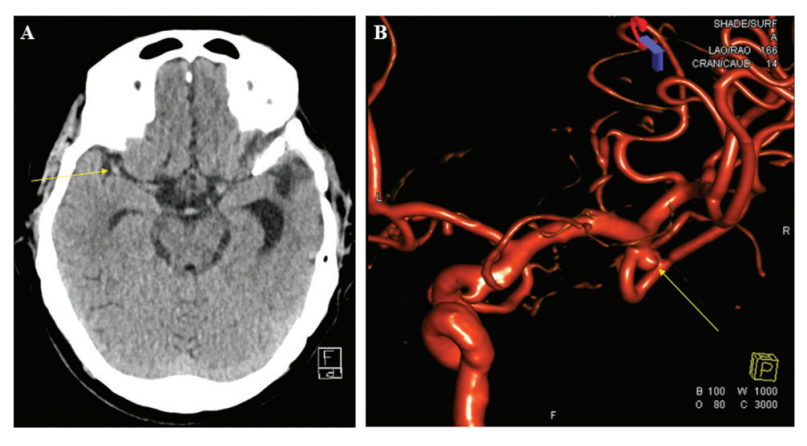

图1:(A)患者1的术前头部CT和(B)脑血管造影三维重建显示右侧长度为3mm的未破裂大脑中动脉动脉瘤。